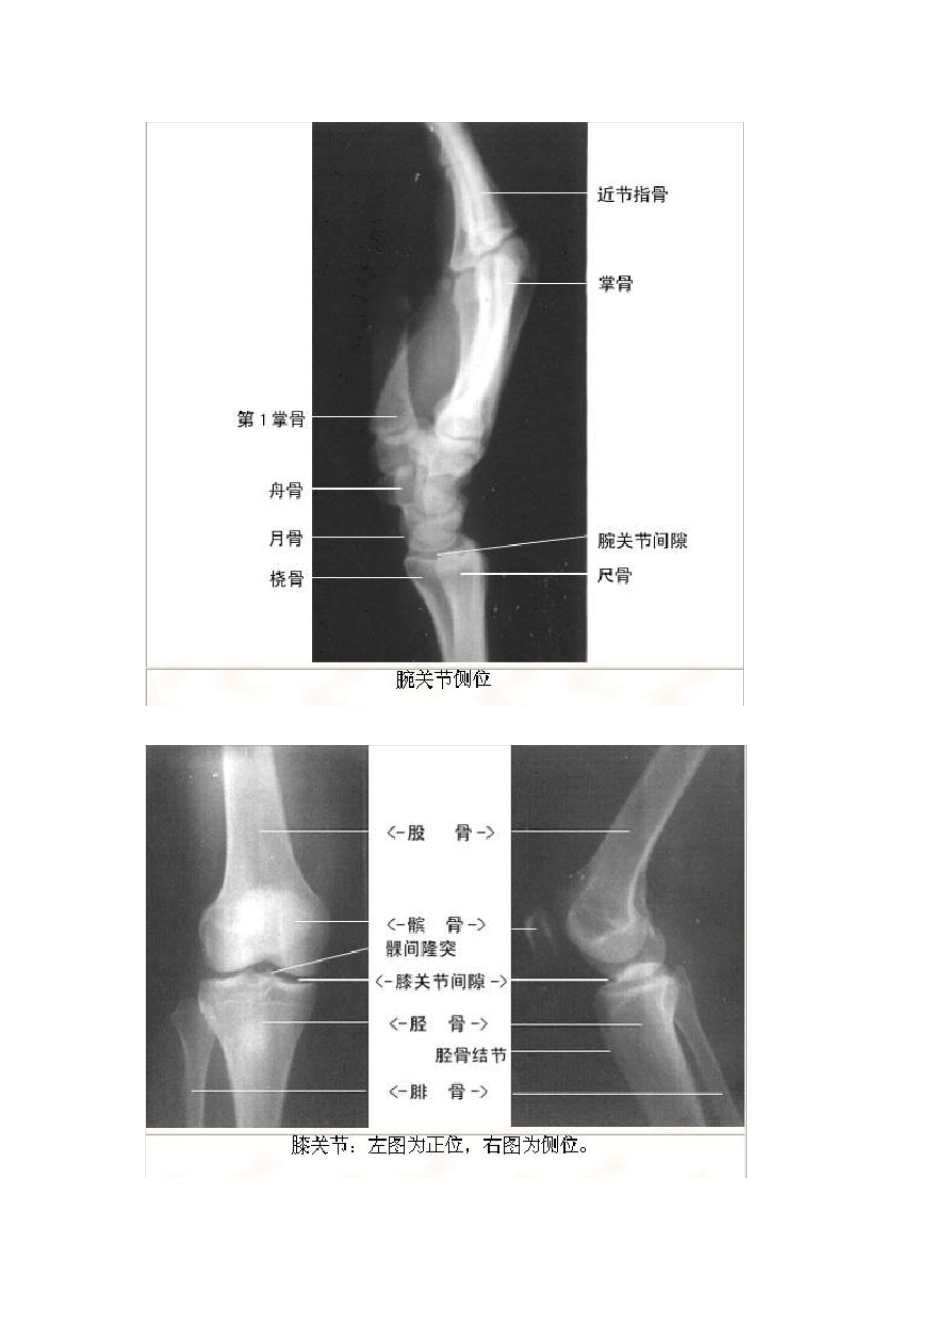

影像看片——X线解剖(绝版收藏)